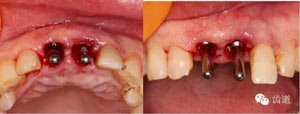

導(dǎo)板引導(dǎo)下定點(diǎn)

腭側(cè)定點(diǎn)

備洞軸向檢查

備洞完成

植入種植體(唇側(cè)留2-3mm jumping gap)

確定植入深度(齦下3-4mm)

小直徑愈合基臺(tái)就位后唇側(cè)植骨

更換大直徑愈合基臺(tái)